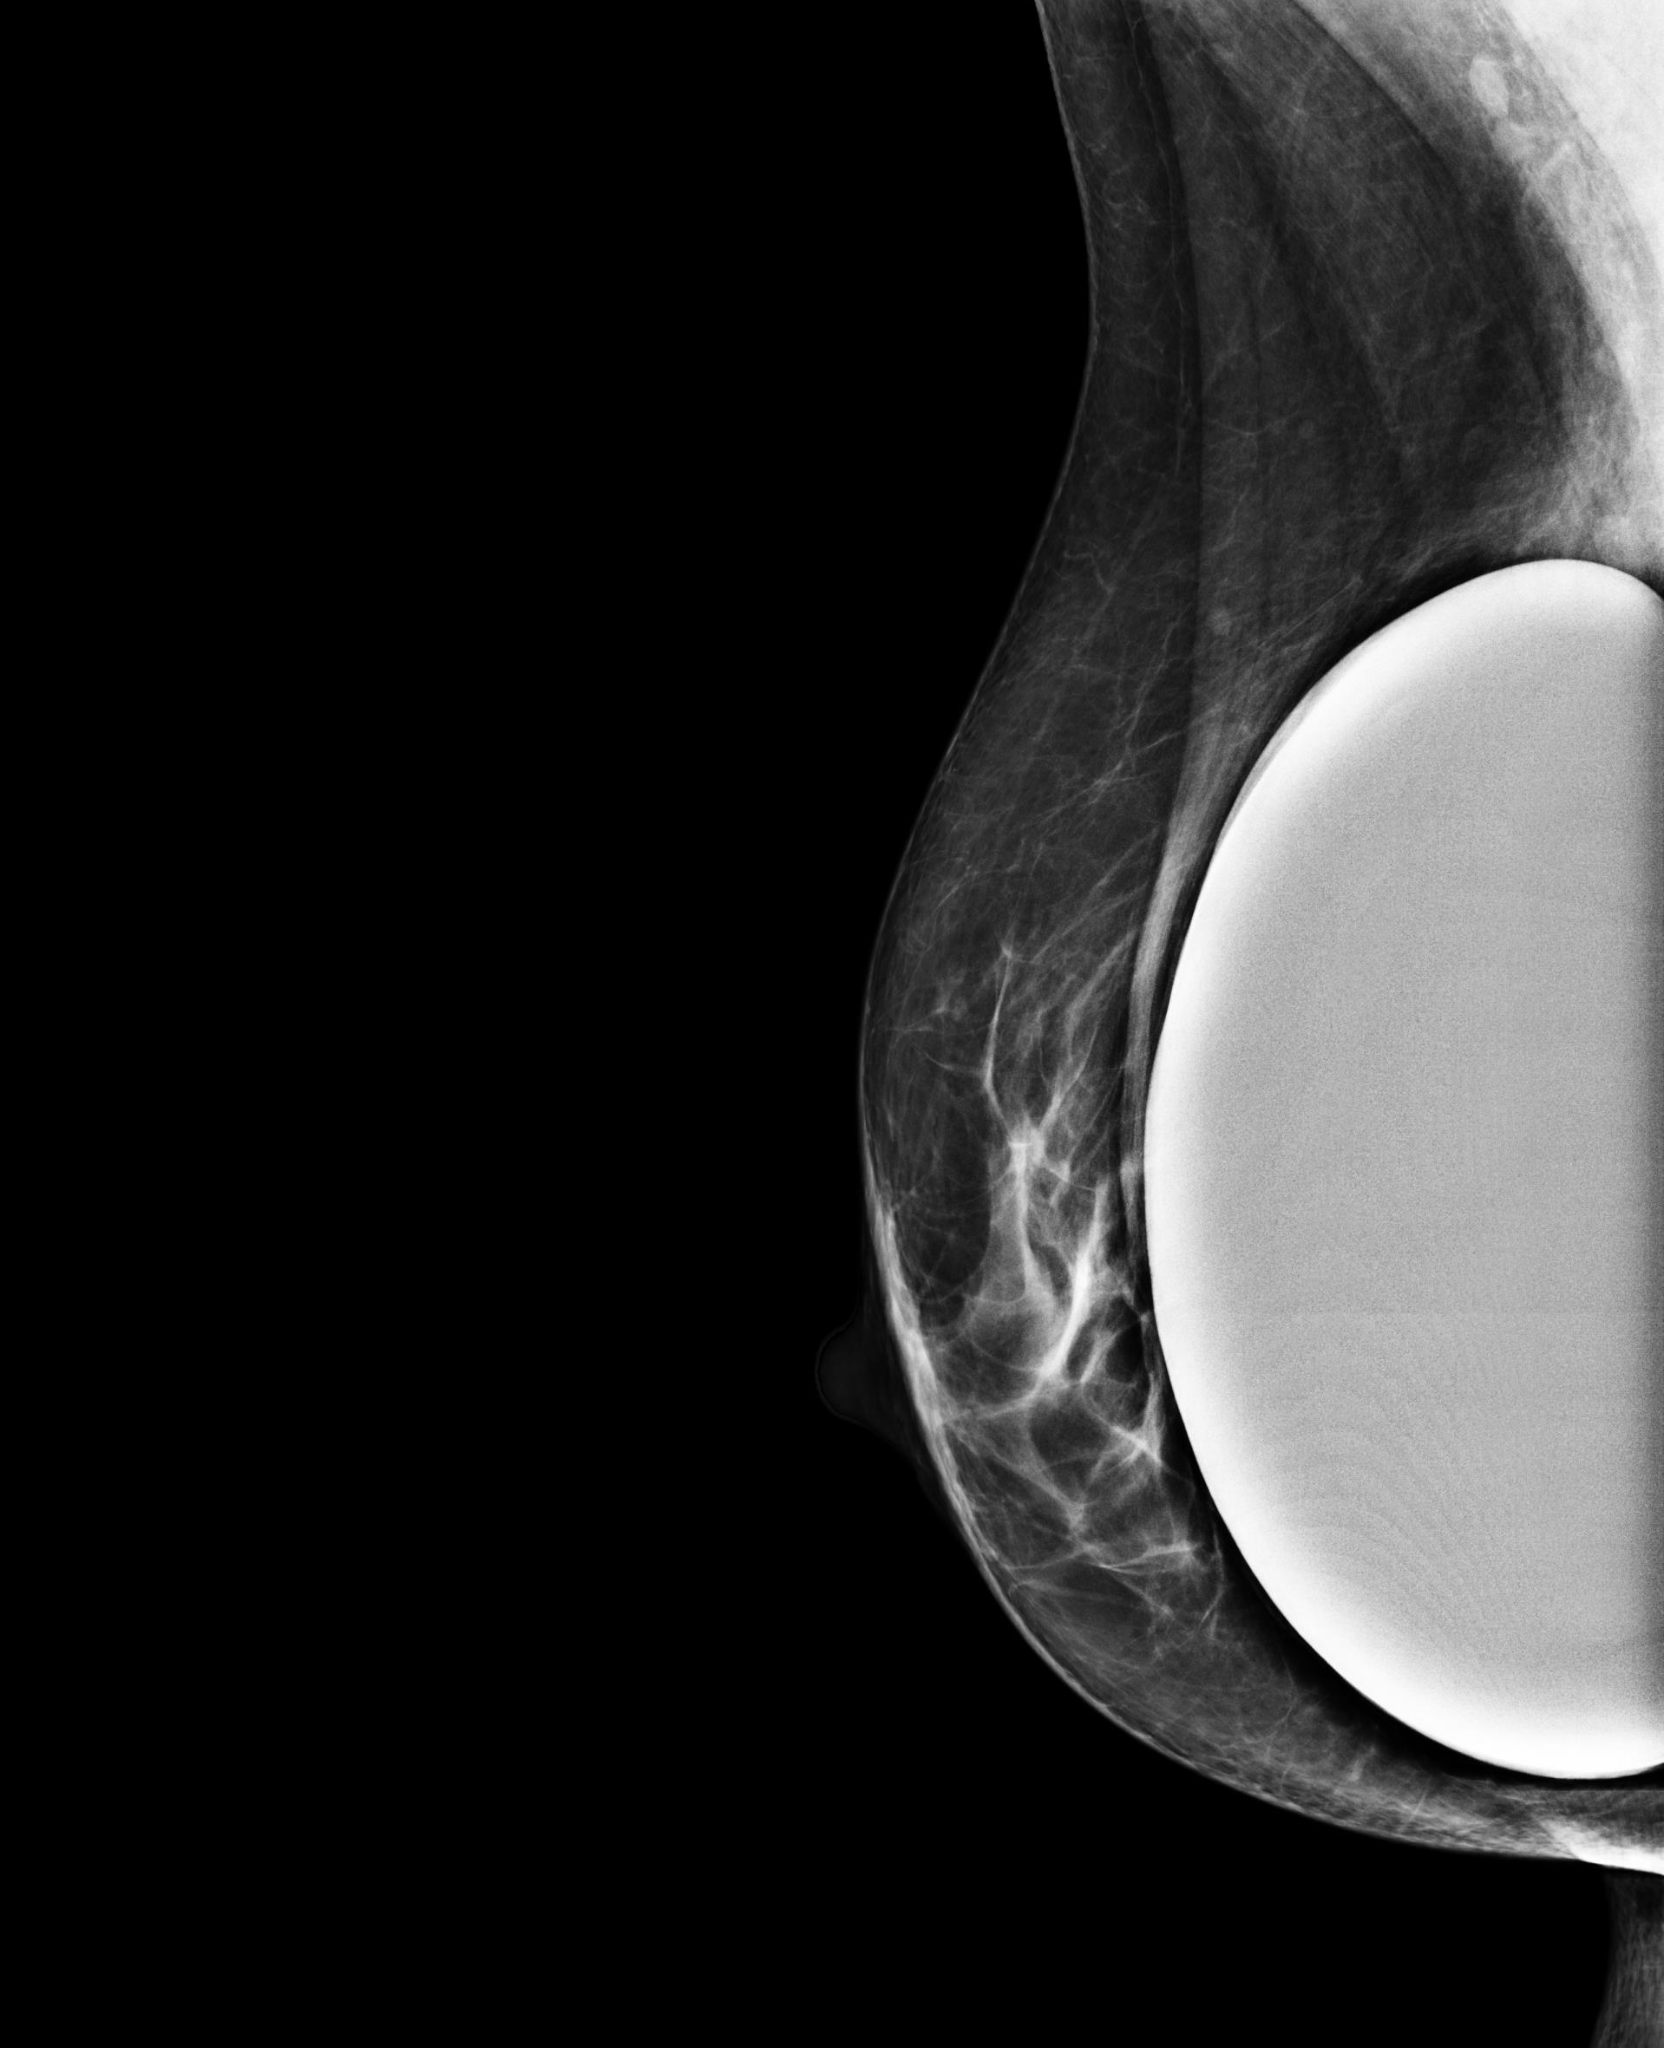

BreastScreen NSW radiographers are trained in taking mammograms for women with breast implants. The pictures below show how special techniques are used to image the breast tissue around implants.